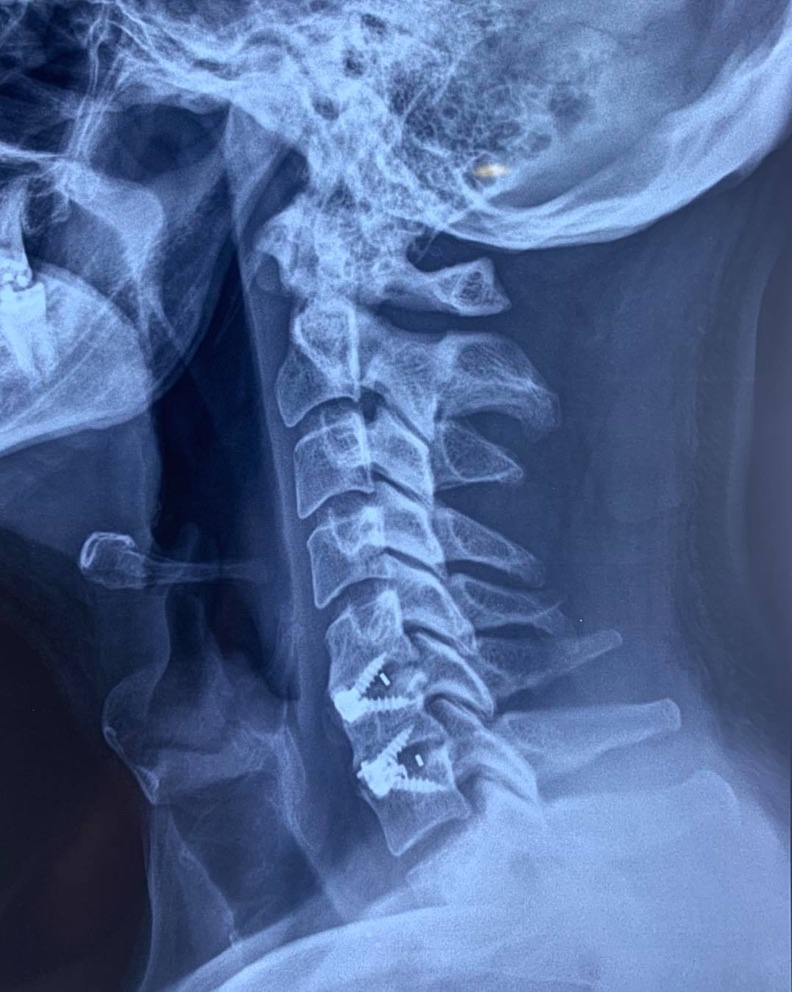

SURGERIES

RESULTS